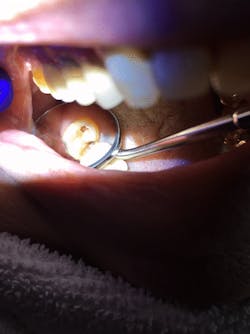

During my next visit with my mom, I performed oral hygiene with special attention to No. 2. I applied the silver diamine fluoride solution and followed it with the potassium iodide solution (figures 1 and 2). It was simple because I used the same technique as I would when applying fluoride varnish and with the caution of disclosing solution.

Figure 1: No. 2 prior to the Riva Star application

Figure 2: No. 2 after the application of Riva Star silver diamine fluoride and potassium iodide solution. Note the creamy white precipitate from the potassium iodide solution.